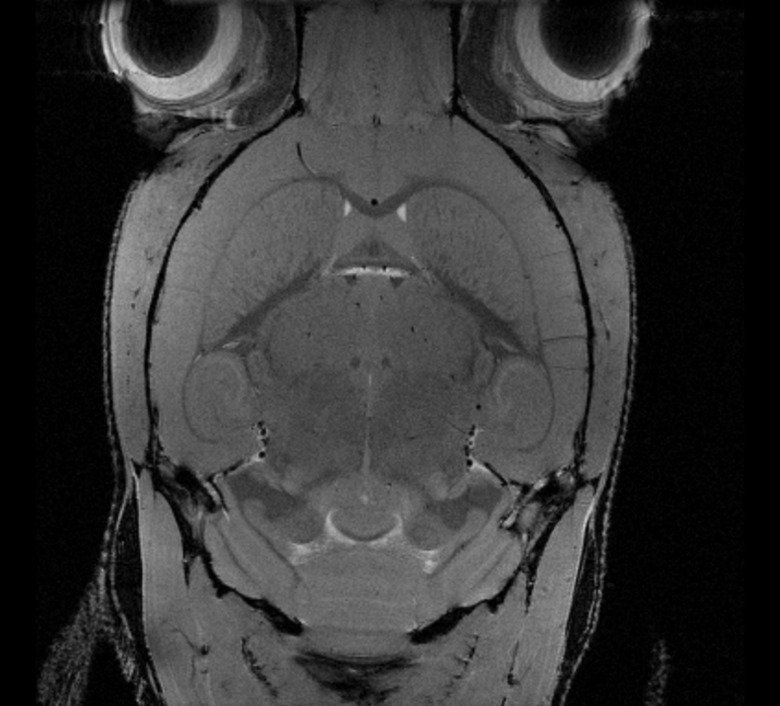

MRI images examples

Rat brain